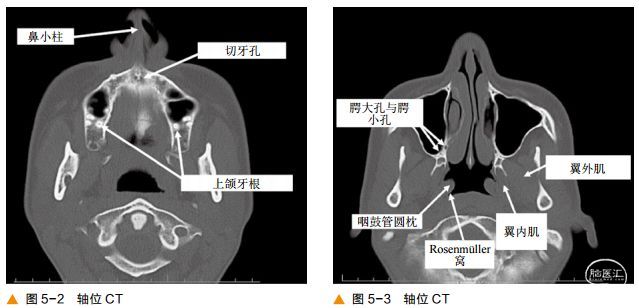

一、轴位图像